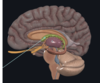

Label this

What are we Looking at?

Substania Nigra in the midbrain

what is the Green structure?

caudate nucleus

what is the structure in Green?

thalamus